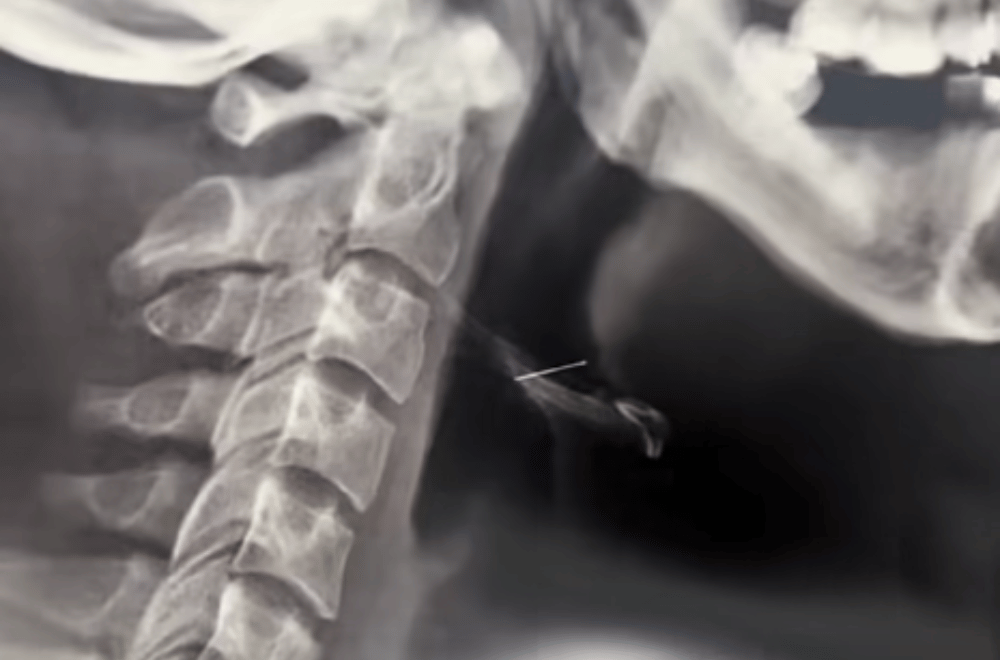

His parents rushed him to the emergency room, where an X-ray confirmed the missing wire was lodged in his throat.

“Parang naka-slant siya. Sinabi na ng doktor na kailangan nilang mag-schedule ng isang ENT doctor,” Jocson said.

The wire, which measured nearly one and a half inches, was eventually found and extracted. “Medyo mahirap daw siyang hanapin pero eventually nahanap naman nila nasa dulo na daw siya ng lalamunan ko. Yung wire na nalunok ko is almost an inch and a half. Mahaba talaga siya,” he said.